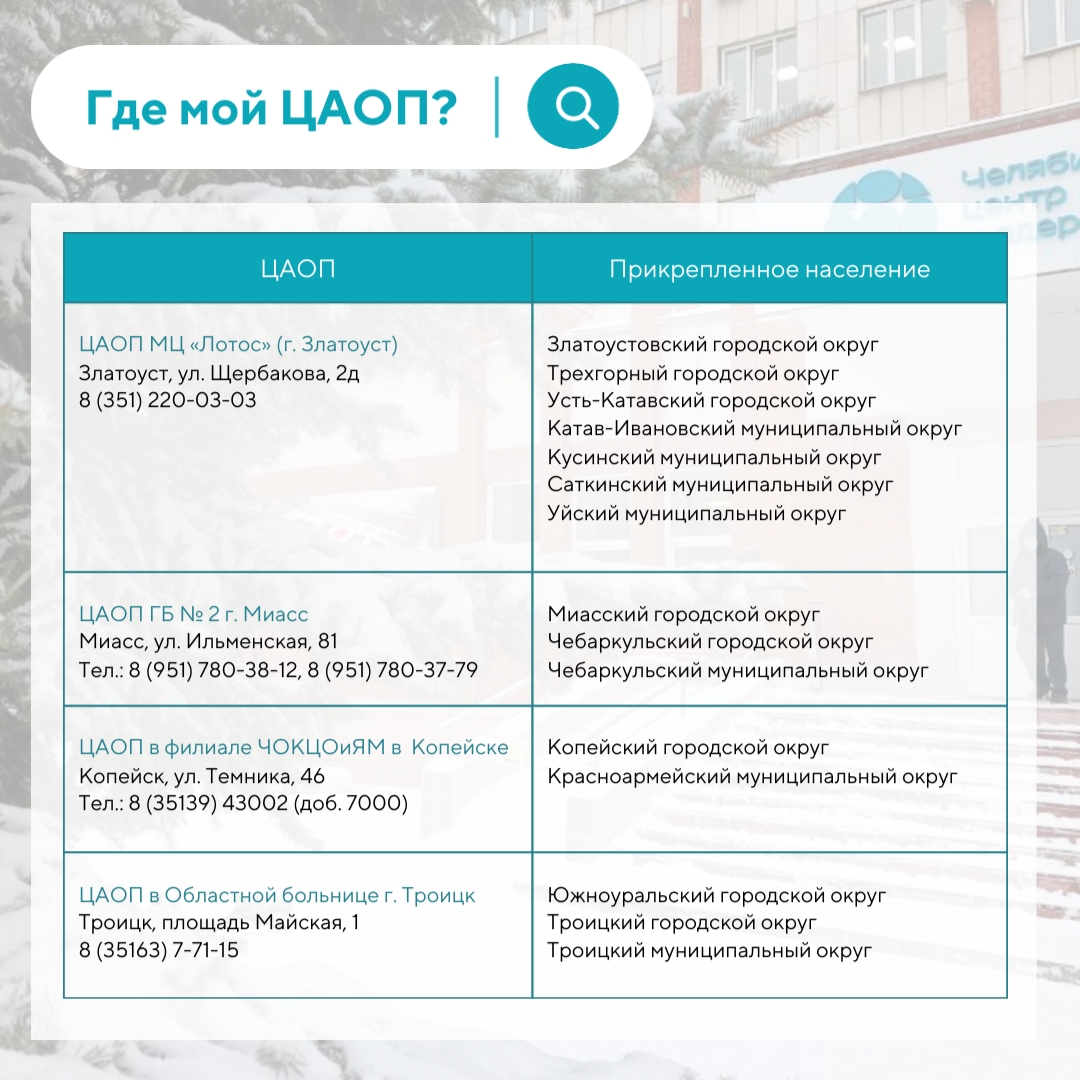

В Челябинской области пациенты прикреплены к конкретным Центрам амбулаторной онкологической помощи, а найти свой можно в карточках:

В Челябинской области пациенты прикреплены к конкретным Центрам амбулаторной онкологической помощи, а найти свой можно в карточках:

Инфографика предоставлена пресс-службой ЧОКЦОиЯМ

Инфографика предоставлена пресс-службой ЧОКЦОиЯМ